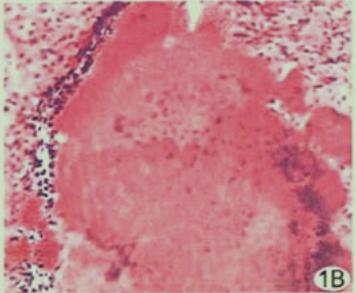

揭晓答案:放线菌感染(图3),空洞悬浮气泡征高度提示肺部放线菌病。

图3 放线菌感染

图3 放线菌感染图4也是肺部空洞悬浮气泡征,最终诊断也是肺部放线菌病。